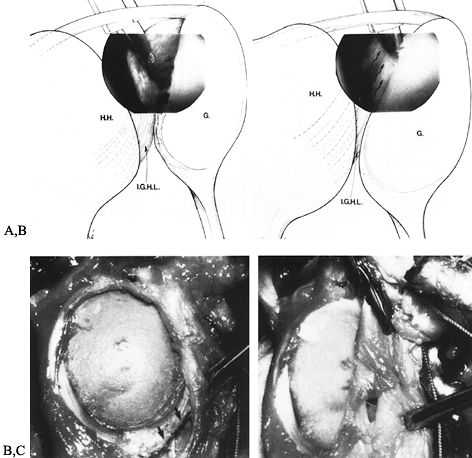

![]() |

Figure 80.4. Arthroscopic view demonstrates normal anterior capsular ligamentous anatomy as viewed through a posterior arthroscopic portal (H.H., humeral head; G, glenoid; B, biceps tendon; S.G.H.L., superior glenohumeral ligament; S.S., subscapularis; M.G.H.L., middle glenohumeral ligament; I.G.H.L.,

inferior glenohumeral ligament). (From Turkel SJ, Panio MW, Marshall JL, Girgis FG. Stabilizing Mechanisms Preventing Anterior Dislocation of the Glenohumeral Joint. J Bone Joint Surg [Am] 1981;63:1209, with permission.) |